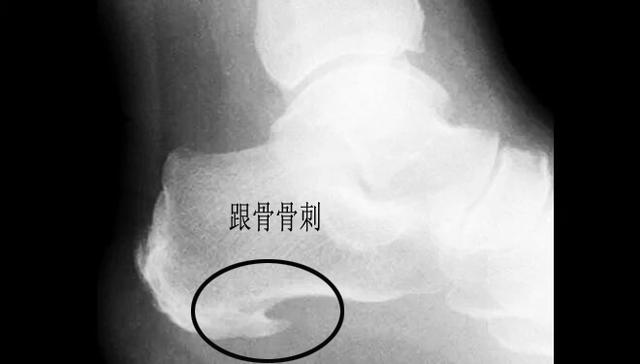

跟骨骨刺导致的跟痛

据数据统计,诱发足跟疼痛的诸多因素当中,跟骨骨刺占其中的15%,但是谢医生本人对这个几率存疑,因为这个几率太高了,临床上太多的患者足跟疼痛特别严重,但是并没有任何的跟骨骨刺。很多体检发现有巨大跟骨骨刺的患者追问病史反而没有丝毫症状。

谢医生认为这些骨刺究其原因,还是因为足底筋膜受到了刺激,在于跟骨连接的部位出现了撕裂、出血,有一些患者在这个部位出现了钙化,最终导致了骨刺的形成。

跟骨骨刺的治疗

无论是否是骨刺诱发的足跟下方的疼痛,只要存有症状,都可以参照足底筋膜炎的治疗方案,治疗建议以保守治疗为主。即使骨刺再大也不建议采取手术切除的办法治疗,很可能手术无效。

针对较大的跟骨骨刺暂时不建议采取冲击波治疗的办法,可能会导致骨刺骨折。